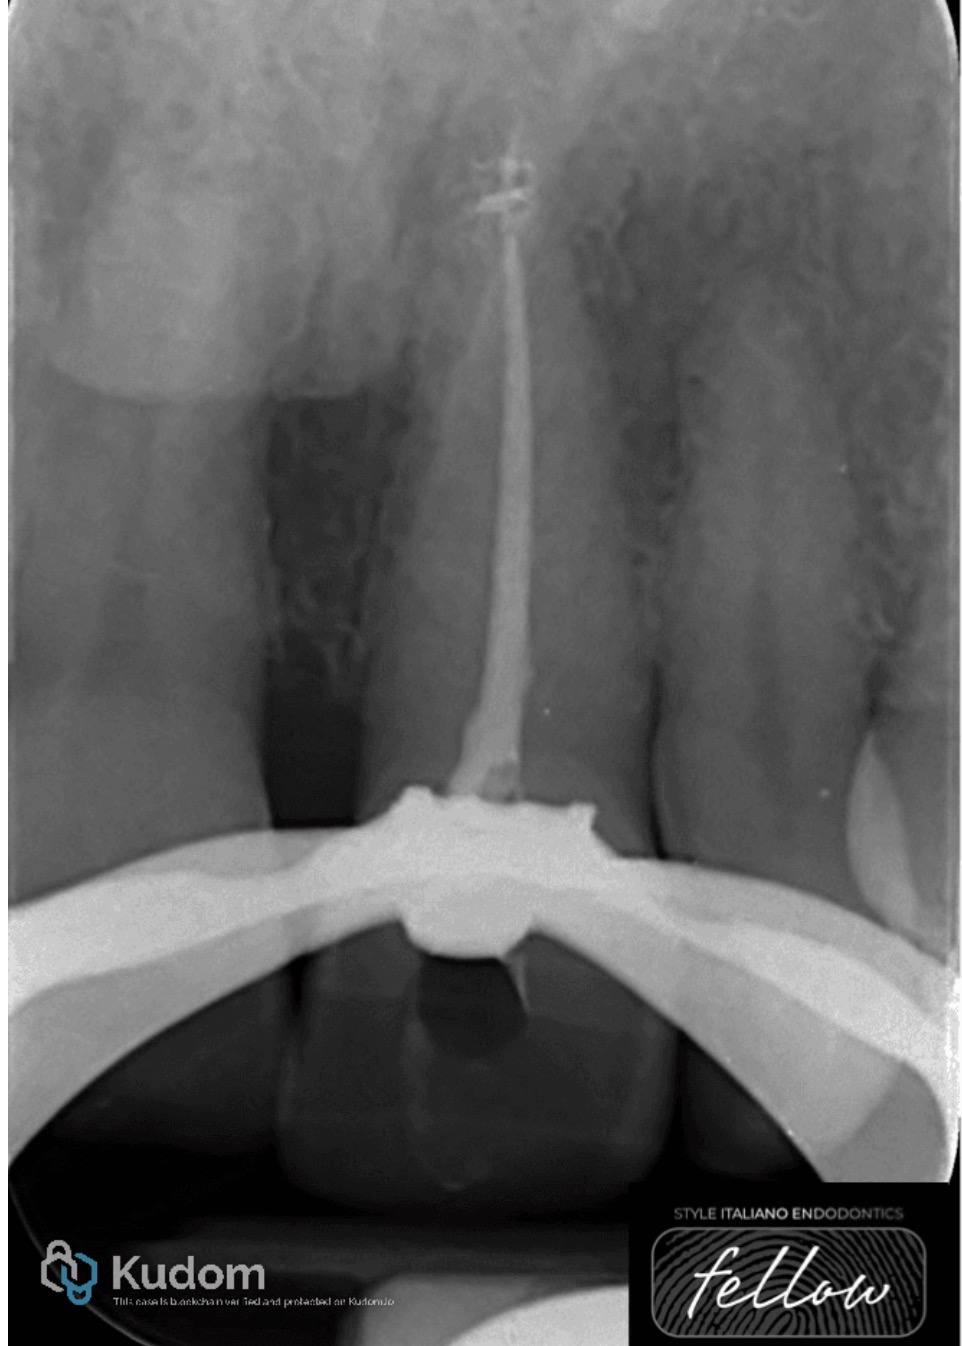

Fig. 2

The operative field was isolated under a rubber dam. An access cavity was prepared through the palatal surface, and necrotic pulp tissue was removed. Root canal treatment was performed with copious irrigation using 5.25% sodium hypochlorite (NaOCl), ultrasonically activated, followed by mechanical instrumentation with ProTaper Gold files.